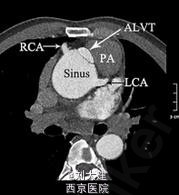

心脏超声和多层 CT 血管造影发现一隧道样结构,伴收缩期顺流和舒张期逆流,该结构起源于主动脉根部,刚好位于扩张的主动脉窦水平之上,缠绕左下进入左心室。最终诊断为 II 型 ALVT(以隧道结构的心脏外主动脉壁动脉瘤伴或不伴瓣膜变形为特征),术中探查后明确诊断,手术关闭隧道后患者表现良好。